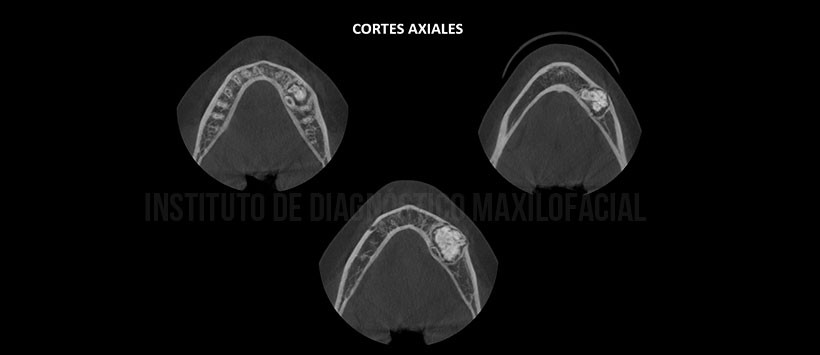

A la evaluación de la tomografía volumétrica (CBCT) en cortes axiales (Figura 2), coronales (Figura 3), transaxiales (Figura 4) y tangenciales (Figura 5) se aprecia múltiples imágenes hiperdensas de diferentes formas y tamaños con aspecto a piezas dentarias (denticulos), delimitado por un halo hipodenso localizado en cuerpo mandibular izquierdo que se extiende en sentido mesio-distal de raíz mesial de pieza 36 a zona apical de pieza 35, en sentido cefálico-caudal del reborde basal mandibular hasta zona próxima a la cresta alveolar. Así mismo se observa desplazamiento caudal del conducto dentario inferior, adelgazamiento y desplazamiento de la tabla ósea vestibular e impactación de la pieza 35 la misma que se encuentra en posición vertical a nivel de la tabla ósea lingual y persistencia de pieza 75.